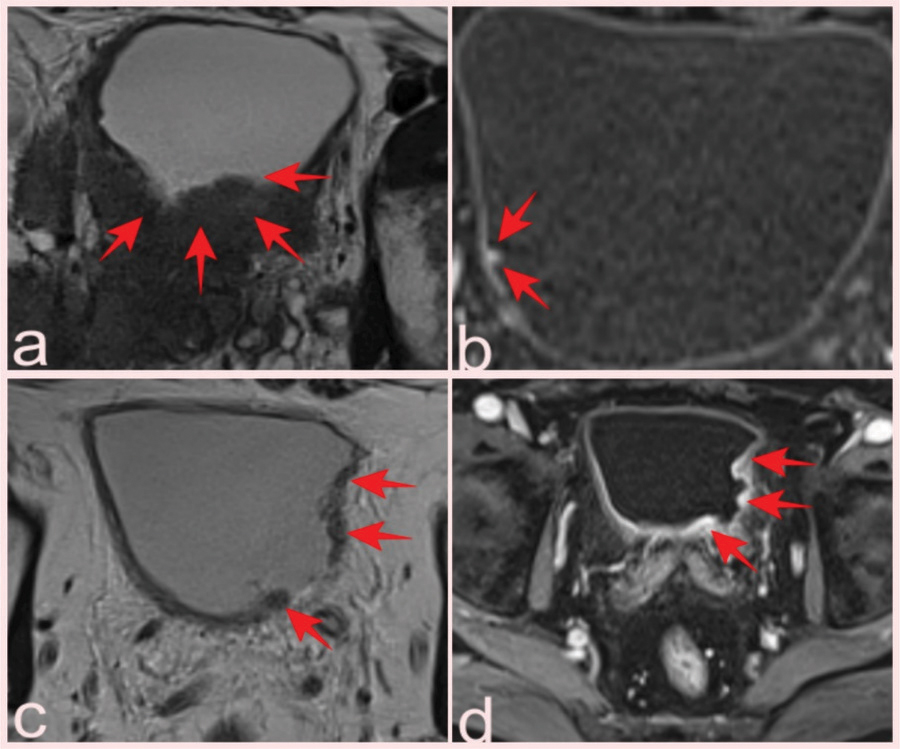

Figure 3

(a) Hypointense soft tissue showing bladder invasion on axial T2-WI in a 74-year-old man with Gleason score 3+4 prostate cancer (arrows). (b) Prostate mpMRI in a 66-year-old patient showed a 0.5 cm lesion on the right posterolateral wall of the bladder that was missed on conventional images but was detected by contrast uptake on DCE images and reported as VI-RADS 1; pathology was benign (Inflamed urothelial tissue) (arrows). T2-WI (c) and DCE (d) images of a 64-year-old patient with a high-grade pT2 tumor classified as VI-RADS 4 (arrows).